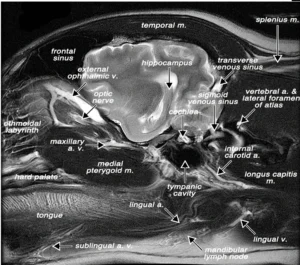

Meridian Zarządzający DU20 "Baihui"

- Rzut oka na lokalizację anatomiczną GV20 i kilku pozostałych punktów wzdłuż meridianu GV (kolorowe ryc. człowiek, MRI proj.strzałkowa: pies)

Nanda G. Robinson " Interactive Medical Acupuncture Anatomy" Tenton Newmedia 2016

- Okolica GV20 jest unerwiana przez nerw czaszkowy V (nerw trójdzielny oraz nerwy z odcinka szyjnego C2 i C3 (m. in. nerw potyliczny mniejszy i większy)

- Podrażnienie nerwu trójdzielnego jest jednym z głównych powodów bólu w obrębie głowy i twarzy.

- Tłumaczy to zastosowanie punktu DU 20 w neuralgii n. trójdzielnego oraz bólach głowy oraz innych zaburzeniach kompleksu trójdzielno-szyjnego (trigeminocervical complex), które spowodowane są często przez problemy stawu skroniowo-żuchwowego, przewodu słuchowego zewnętrznego lub zwyrodnienia odcinka szyjnego

- Bóle zębów oraz zaburzenia mechaniki stawu skroniowo-żuchwowego mogą generować bodźce nocyceptywne, które będą zwiększać sensytyzację dróg nerwowych obszaru uszno-czołowego, prowadząc do mimowolnych drżeń, np. obszaru głowy a nawet zaburzeń równowagi i zaburzeń chodu

Obszar meridianu GV jest też obszarem o bogatym unaczynieniu, sąsiaduje z przednią zatoką strzałkową, która drenuje boczne powierzchnie przednich półkul mózgowych. Tu w największej ilości uchodzą ziarnistości pajęczynówkowe w których zachodzi proces wchłaniania płynu mózgowo-rdzeniowego z przestrzeni podpajęczynówkowej do systemu krwionośnego.